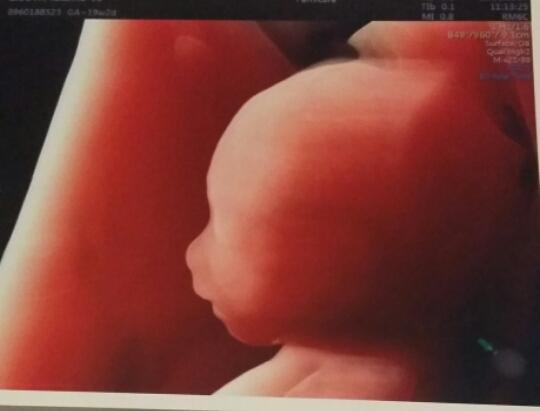

20tt